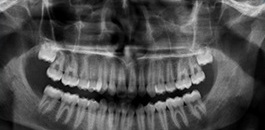

Radiografia panorâmica digital

Exame realizado em apenas 17 segundos. Nosso equipamento permite a combinação de 9 diferentes tipos de arcadas, permitindo imagens nítidas e com altíssima definição.